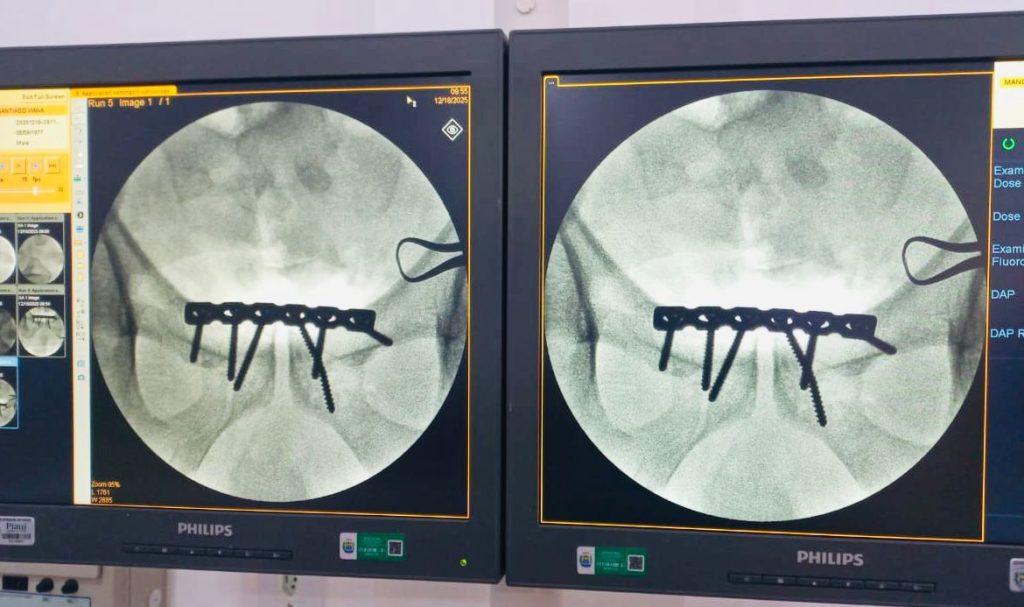

O paciente, do sexo masculino, foi vítima de trauma automobilístico, apresentando fratura do anel pélvico do tipo “livro aberto”, considerada um trauma grave. Até então, casos como esse exigiam a transferência para unidades de referência em Teresina. Nesta ocasião, todo o tratamento cirúrgico foi realizado no próprio HRCR, com suporte completo de anestesia, enfermagem, materiais adequados e segurança assistencial.